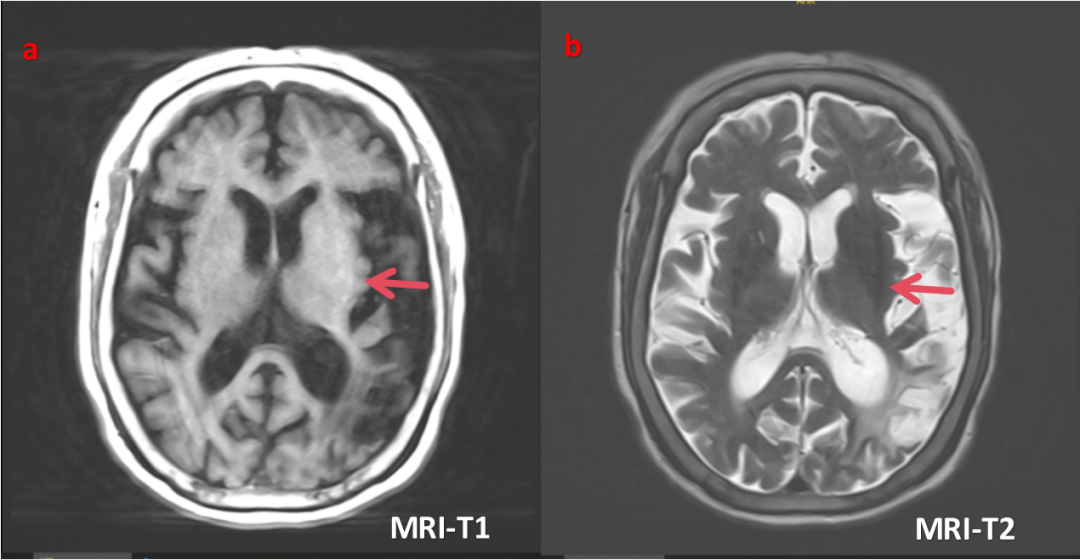

磁共振颅脑平扫+MRA:脑内多发腔梗、缺血灶;右侧枕叶及左侧颞枕叶软化灶伴周围胶质增生;左侧基底节区少许斑片状TWI高信号及TW2低信号;DWI右侧小脑稍高信号,伪影可能;老年性脑改变;脑动脉粥样硬化

改变,右侧颈内动脉颅内段未见显示,两侧大脑中动脉狭窄。(图a、b)

注:a、b图为患者入院当天时(2025-10-23)颅脑MR图像,提示左侧基底节区斑片状TWI高信号及TW2低信号;

c、d 图为患者入院4天后(2025-10-27跌倒坠床)完善头颅CT图像,提示左侧基底节区高密度影,CT值40HU,无水肿

及占位效应,结合MR,此处高密度影不考脑出血

相关。

高血糖可导致多种神经系统损害,当并发运动障碍时,多表现为偏身舞蹈症,当急性发作时典型的影像表现为对侧纹状体MRI T1WI 高信号,T2WI 则为多变信号,边界清晰,无水肿现象,CT 平扫高密度为该并发症的特异改变。虽然糖尿病纹状体病影像表现具有明显特征性,但当表现出明显 T1WI 高信号、T2WI 低信号及 CT 高密度时,仍需要与出血相鉴别。急性脑内出血周围可见明显水肿信号并且当豆状核、尾状核头均受累时内囊会受累,且 DWI 可明显弥散受限,1~2 周复查糖尿病纹状体病影像改变不明显但是出血改变明显,这些均是重要鉴别点。 DS 患者影像学检查具有特征性表现,患肢对侧纹状体,主要是尾状核头和壳核,发病初期 CT 表现为高密度灶,信号不均匀,急性期呈片状改变,MRI 上 TWI 基底节区尤其是壳核呈高信号,在基底节其他结构性或代谢性损害中未见到这种影像学改变。此影像学表现的解释

虽然 DS 表型存在多样性,但典型的 DS 存在以下 3 个特点即可做出诊断:1.血糖控制较差的糖尿病;2.亚急性单侧肢体舞蹈/投掷样运动障碍;3.舞蹈肢体对侧纹状体特征性MRI为 T1WI 高信号异常影像学表现。这类患者在控制血糖、氟哌啶醇+氯硝西泮治疗后患者舞蹈症状可明显缓解。DS 的 MRI 敏感性为 95.33%,CT 敏感度为 78.86%。当高血糖患者出现舞蹈样运动障碍,而MRI-T1序列未见纹状体高信号,需要做大量的鉴别诊断,排除舞蹈症的其他病因,如血管性、自身免疫性、中毒性、感染性、肿瘤性、炎症性、药物性等,才能做出糖尿病纹状体病诊断。

本例患者中年女性,本次表现为突发右上肢及右侧面部不自主运动,平素糖尿病管理较差,入院血糖水平高达28.31 mmol/L,呈非酮症非高渗状态,MRI在左侧(舞蹈运动障碍肢体对侧)基底节区出现特征性T1WI 高信号表现,头颅CT左侧基底节区片状高密度影,血糖控制良好后症状完全消失,符合DS诊断的特征性改变。患者无肝病史,肝功能、甲功能、血钙磷、铜蓝蛋白无异常,颅内无钙化灶,查体无K-F环,排除亨廷顿舞蹈症、肝豆状核变性、基底节钙化、甲状旁腺功能减退、风湿免疫相关疾病等;患者无发热,无毒物及一氧化碳中毒,无免疫系统相关疾病等,排除药物、中毒、免疫、细菌等相关获得性舞蹈症。患者糖尿病纹状体病诊断成立。但该患者需后续进行随访,如颅脑影像学检查提示右侧基底节区高密度影缩小或消退,更支持DS诊断。